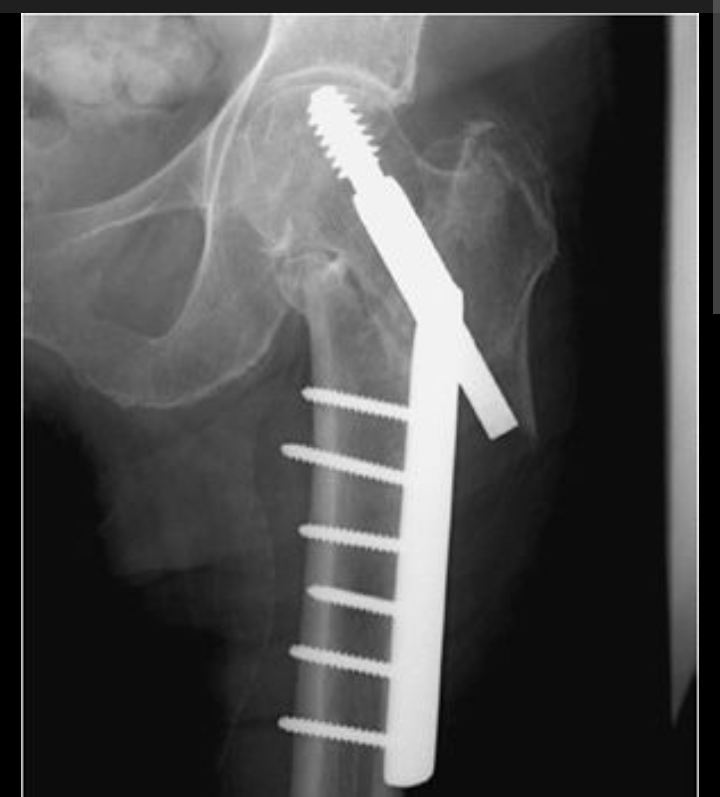

Recently, during an extreme rainstorm, Ross took a serious fall while running for shelter and broke his hip. He required emergency surgery and now faces a long recovery, expected to be out of work for approximately 8 months.